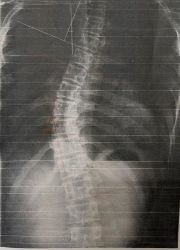

レントゲンのビフォーアフター)

写真1(施術前) 写真2(5か月後)

○コブ角上27度⇒25度(2度改善)、下40度⇒33度(7度改善)

※コブ角は専門医の診断